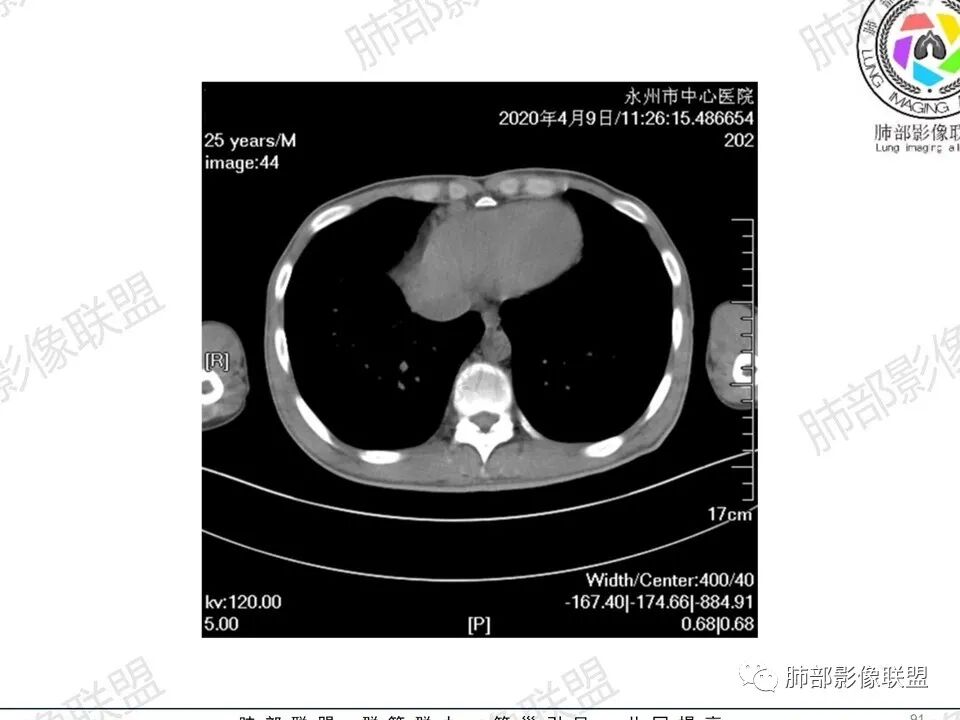

3、影像表现:双肺散在斑片影及结节影,部分结节内可见血管穿行,斑片影沿支气管血管束分布,近胸膜侧病变收缩不明显。部分中央淋巴间质增厚,小叶间隔增厚。病灶内支气管穿行,部分支气管略扩张。局部小结节呈串珠样改变。纵隔、肺门区、锁骨上及腋窝淋淋巴结肿大,部分有融合。心腔低密度。脾大。

5.双肺门及纵隔淋巴结显著增大,这改变相当显眼。这里强调“双肺门”及“多发”!

增大的淋巴结密度偏低且均匀。此外患者有体表淋巴结增大。

6.心腔密度减低。提示可能存在贫血。

7.脾脏增大。